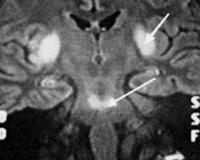

• МРТ головного мозга. На изображениях видны гиперинтенсивные (светящиеся) участки демиелинизации, симметричные очаги овальной формы в полушариях головного мозга в сочетании с повреждениями типа «бабочка» или «трезубец» на мосту. Для лучшей проверки демиелинизирующих процессов используется МРТ в Т2-режиме.